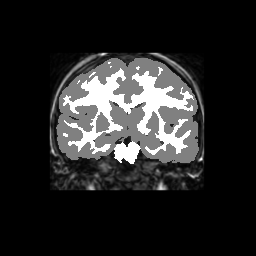

Test/Retest Reliability

FSL was run on each scan in the Brain Segmentation Testing Protocol (BSTP) between-scanner test/retest dataset. Select a subject below to see volumes for each subject across the subject's scans.